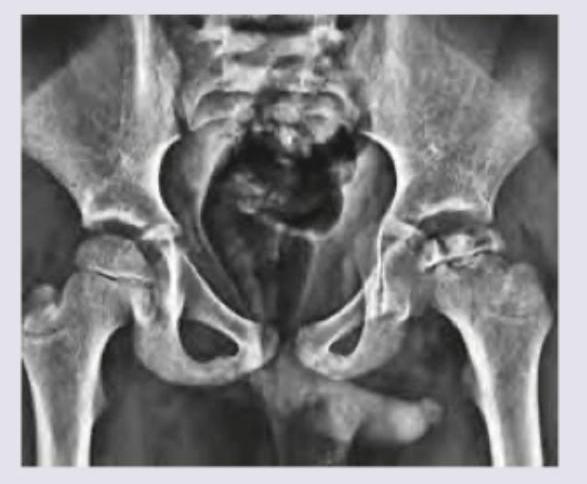

A 5-year-old child presents with limp and pain in left thigh. The mother remarks that her child was always very active and was always running and jumping around, but has restricted activity for last 3 months. What does the given X-ray bilateral hip joint show?

Explanation: ***Legg-Calve-Perthes disease*** - The X-ray shows changes consistent with **avascular necrosis of the femoral head**, characterized by **flattening and fragmentation of the epiphysis** on the left, which is typical for Legg-Calve-Perthes disease in a 5-year-old child presenting with limp and pain. - The clinical presentation of a **5-year-old child** with a limp, pain in the thigh, and progressive restriction of activity over 3 months is highly suggestive of Legg-Calve-Perthes disease. *Developmental dysplasia of hip* - This condition is typically diagnosed in **infancy or early childhood** and involves an **abnormal development of the hip joint**, often with **acetabular dysplasia** and/or **femoral head subluxation or dislocation**. - The X-ray findings in this case (specifically, the apearance of the femoral head itself) are not consistent with the typical features of DDH, which would show an underdeveloped or shallow acetabulum and/or a displaced femoral head, rather than the fragmentation seen. *Slipped capital femoral epiphysis* - SCFE primarily affects **adolescents** (typically 10-16 years old) during periods of rapid growth and presents with a **posterior and inferior displacement of the femoral epiphysis** relative to the femoral neck. - The patient's age (5 years old) is outside the typical age range for SCFE, and the radiological findings of **flattening and fragmentation** are not characteristic of this condition. *TB hip* - **Tuberculosis of the hip** typically causes **joint space narrowing**, **osteolysis**, and sometimes **abscess formation** or **periarticular osteopenia**, often with a more insidious onset and systemic symptoms. - While TB hip can present with limp and pain, the specific **radiographic changes of fragmentation and flattening of the femoral head epiphysis** seen on this X-ray are not classic for TB and are more indicative of avascular necrosis.